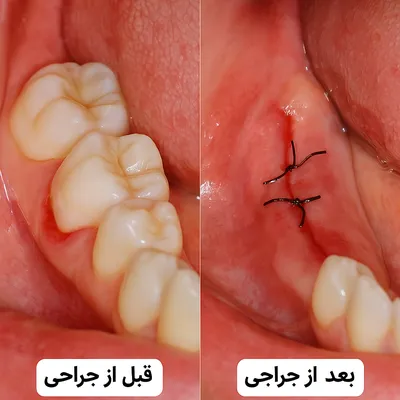

تصویر قبل و بعد جراحی دندان نهفته همراه با بخیه و بهبود لثه

بهطور خلاصه، تمامی این عوامل دستبهدست هم میدهند تا قیمت نهایی مشخص شود. بنابراین بهتر است بیمار بداند چرا تعرفهها در مراکز مختلف یا حتی بین دو دندان عقل خودش میتواند متفاوت باشد. این شفافیت، هم دغدغه مالی او را کمتر میکند و هم تصمیمگیری را آسانتر.

عوارض احتمالی جراحی و ارتباط با هزینه

بخش مهمی از برآورد هزینه جراحی دندان عقل نهفته به عوارض پس از عمل بستگی دارد. در برخی بیماران، شرایط خاص یا مراقبت ناکافی میتواند باعث مراجعات بیشتر و افزایش هزینههای دندانپزشکی شود. مهمترین موارد عبارتند از:

-

التهاب و تورم لثه: معمولاً طبیعی است، اما در صورت شدید بودن نیاز به دارو یا مراجعه مجدد دارد.

-

درد بعد از جراحی: اگر بیش از حد طولانی شود، ممکن است نیاز به درمان دارویی یا کنترل تخصصی داشته باشد.

-

عفونت محل بخیه دندان عقل: مصرف آنتیبیوتیک و ویزیتهای اضافی میتواند هزینه نهایی را بالا ببرد.

-

باز شدن بخیه یا خونریزی طولانی: گاهی نیاز به بخیه مجدد یا تعویض پانسمان دارد.

-

آسیب احتمالی به عصب یا استخوان فک: موارد نادر ولی پرهزینه که گاهی به جراحی تکمیلی نیاز پیدا میکند.

به همین دلیل، بخشی از اختلاف در هزینه جراحی دندان عقل نهفته به احتمال بروز این عوارض و درمانهای تکمیلی پس از عمل مربوط میشود. رعایت دقیق توصیههای پزشک بهترین راه برای کاهش این هزینههای اضافی است.